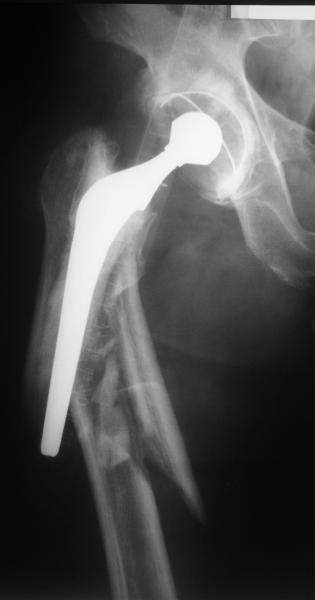

Reminded me of a case I did a couple years ago - 30 year old woman with juvenile rheumatoid arthritis and a nonunion below her stem. Fixed with retrograde nail which docked with the stem and a lateral locking plate. Image attached. One of the companies should come up with a stem design and nail system that anticipates this need.